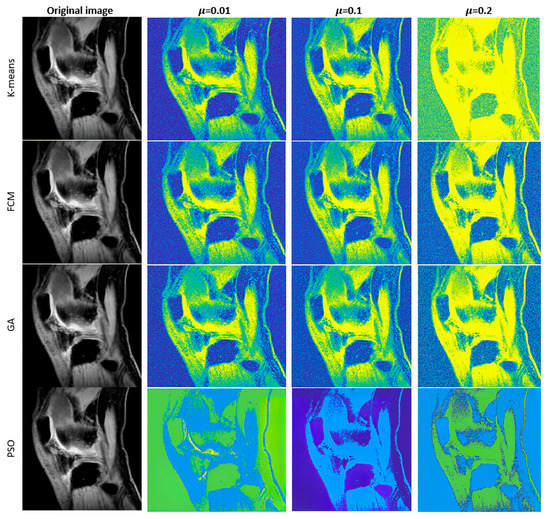

Novel Hybrid Optimized Clustering Schemes with Genetic Algorithm and PSO for Segmentation and Classification of Articular Cartilage Loss from MR Images

by Jan Kubicek, Alice Varysova, Martin Cerny, Jiri Skandera, David Oczka, Martin Augustynek and Marek Penhaker

Mathematics 2023, 11(4), 1027; https://doi.org/10.3390/math11041027 - 17 Feb 2023

Medical image segmentation plays an indispensable role in the identification of articular cartilage, tibial and femoral bones from magnetic resonance imaging (MRI). There are various image segmentation strategies that can be used to identify the knee structures of interest. Among the most popular [...] Read more.

Medical image segmentation plays an indispensable role in the identification of articular cartilage, tibial and femoral bones from magnetic resonance imaging (MRI). There are various image segmentation strategies that can be used to identify the knee structures of interest. Among the most popular are the methods based on non-hierarchical clustering, including the algorithms K-means and fuzzy C-means (FCM). Although these algorithms have been used in many studies for regional image segmentation, they have two essential drawbacks that limit their performance and accuracy of segmentation. Firstly, they rely on a precise selection of initial centroids, which is usually conducted randomly, and secondly, these algorithms are sensitive enough to image noise and artifacts, which may deteriorate the segmentation performance. Based on such limitations, we propose, in this study, two novel alternative metaheuristic hybrid schemes: non-hierarchical clustering, driven by a genetic algorithm, and Particle Swarm Optimization (PSO) with fitness function, which utilizes Kapur’s entropy and statistical variance. The goal of these optimization elements is to find the optimal distribution of centroids for the knee MR image segmentation model. As a part of this study, we provide comprehensive testing of the robustness of these novel segmentation algorithms upon the image noise generators. This includes Gaussian, Speckle, and impulsive Salt and Pepper noise with dynamic noise to objectively report the robustness of the proposed segmentation strategies in contrast with conventional K-means and FCM. This study reveals practical applications of the proposed algorithms for articular cartilage extraction and the consequent classification performance of early osteoarthritis based on segmentation models and convolutional neural networks (CNN). Here, we provide a comparative analysis of GoogLeNet and ResNet 18 with various hyperparameter settings, where we achieved 99.92% accuracy for the best classification configuration for early cartilage loss recognition. Full article

Show Figures

Figure 1